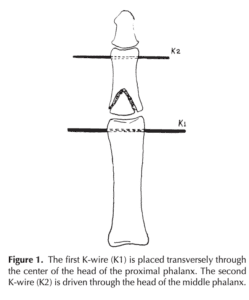

Fixation method for unstable bony mallet finger

A simple fixation method for unstable bony mallet finger A…